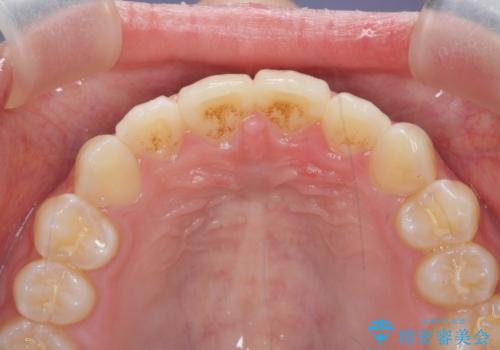

インビザラインライトで行う短期マウスピース矯正治療

- 前歯のガタつきを並べたいたいと、矯正治療を希望され来院されました。

とにかく短期間で前歯だけの治療を行いという希望が強く、全体矯正と前歯だけの部分矯正の仕上がりのイメージを確認したのち14枚のマウスピースで前歯のみの矯正治療を行っていくこととしました。

インビザラインライトは軽度なガタつきや傾斜の改善に用いられる全14枚のマウスピース矯正です。

短期間で治療の終了が見込めるだけでなく、料金もインビザラインフルに比べリーズナブルです。